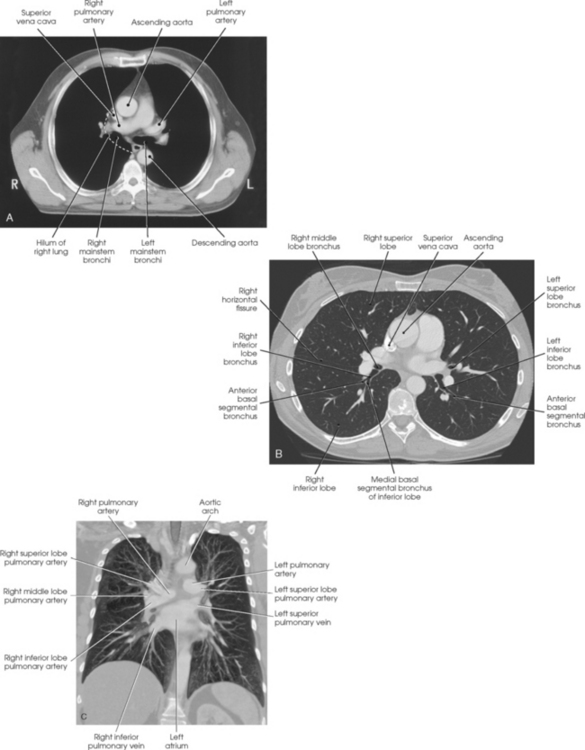

The lungs are the organs of respiration (Fig. 10-4). They are the mechanism for introducing oxygen into the blood and removing carbon dioxide from the blood. The lungs are composed of a light, spongy, highly elastic substance, the parenchyma, and they are covered by a layer of serous membrane. Each lung presents a rounded apex that reaches above the level of the clavicles into the root of the neck and a broad base that, resting on the obliquely placed diaphragm, reaches lower in back and at the sides than in front. The right lung is about 1 inch (2.5 cm) shorter than the left lung because of the large space occupied by the liver, and it is broader than the left lung because of the position of the heart. The lateral surface of each lung conforms with the shape of the chest wall. The inferior surface of the lung is concave, fitting over the diaphragm, and the lateral margins are thin. During respiration, the lungs move inferiorly for inspiration and superiorly for expiration (Fig. 10-5). During inspiration, the lateral margins descend into the deep recesses of the parietal pleura. In radiology, this recess is called the costophrenic angle (see Fig. 10-5, B). The mediastinal surface is concave with a depression, called the hilum, that accommodates the bronchi, pulmonary blood vessels, lymph vessels, and nerves. The inferior mediastinal surface of the left lung contains a concavity called the cardiac notch. This notch conforms to the shape of the heart.

Fig. 10-4 A, Three views of the lung. B, CT axial image through the thorax. Right and left lungs are shown in actual position within thorax and in relation to heart. Note nodule in right anterior lung (arrow). (B, Courtesy Siemens Medical Systems, Iselin, NJ.)